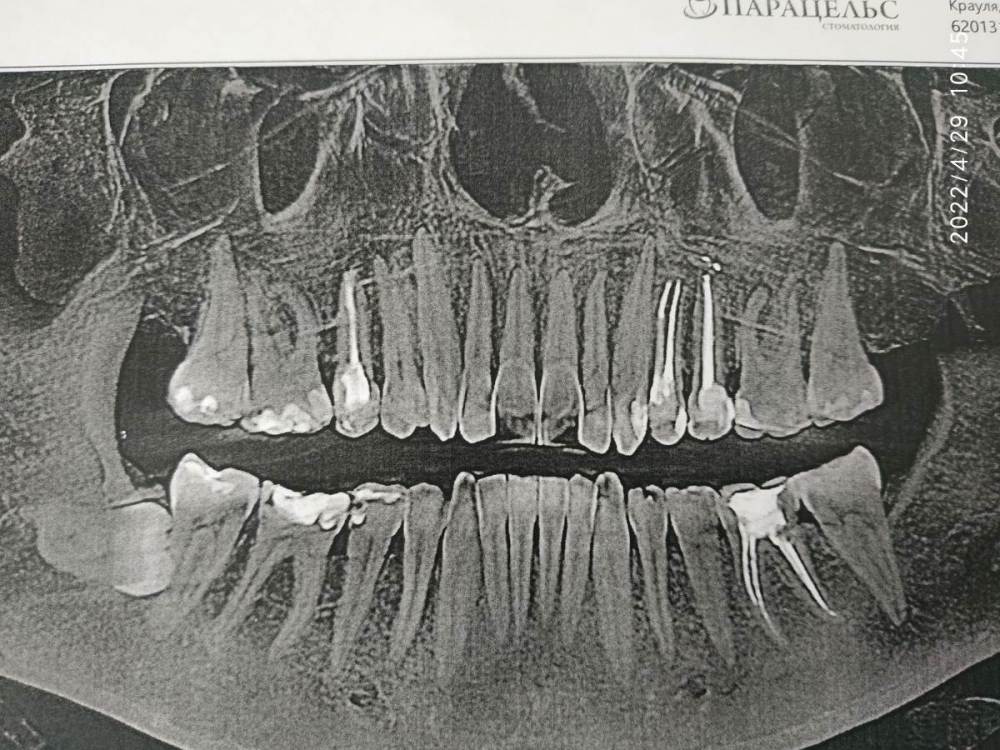

26 апреля побежала уже к другому врачу. Та отправила на КТ, которое показало пульпит в 23 зубе.

Болит вся область: 25, 24, 23 и 21. Особенно меня беспокоит 21. Он вообще здоровый, нелеченый зуб. А заныл просто дико!

Не понимаю, что с 21 зубом. Он особенно сильно ноет. После постукивания при осмотре. Врач утверждает, что пройдет, в него просто отдает.